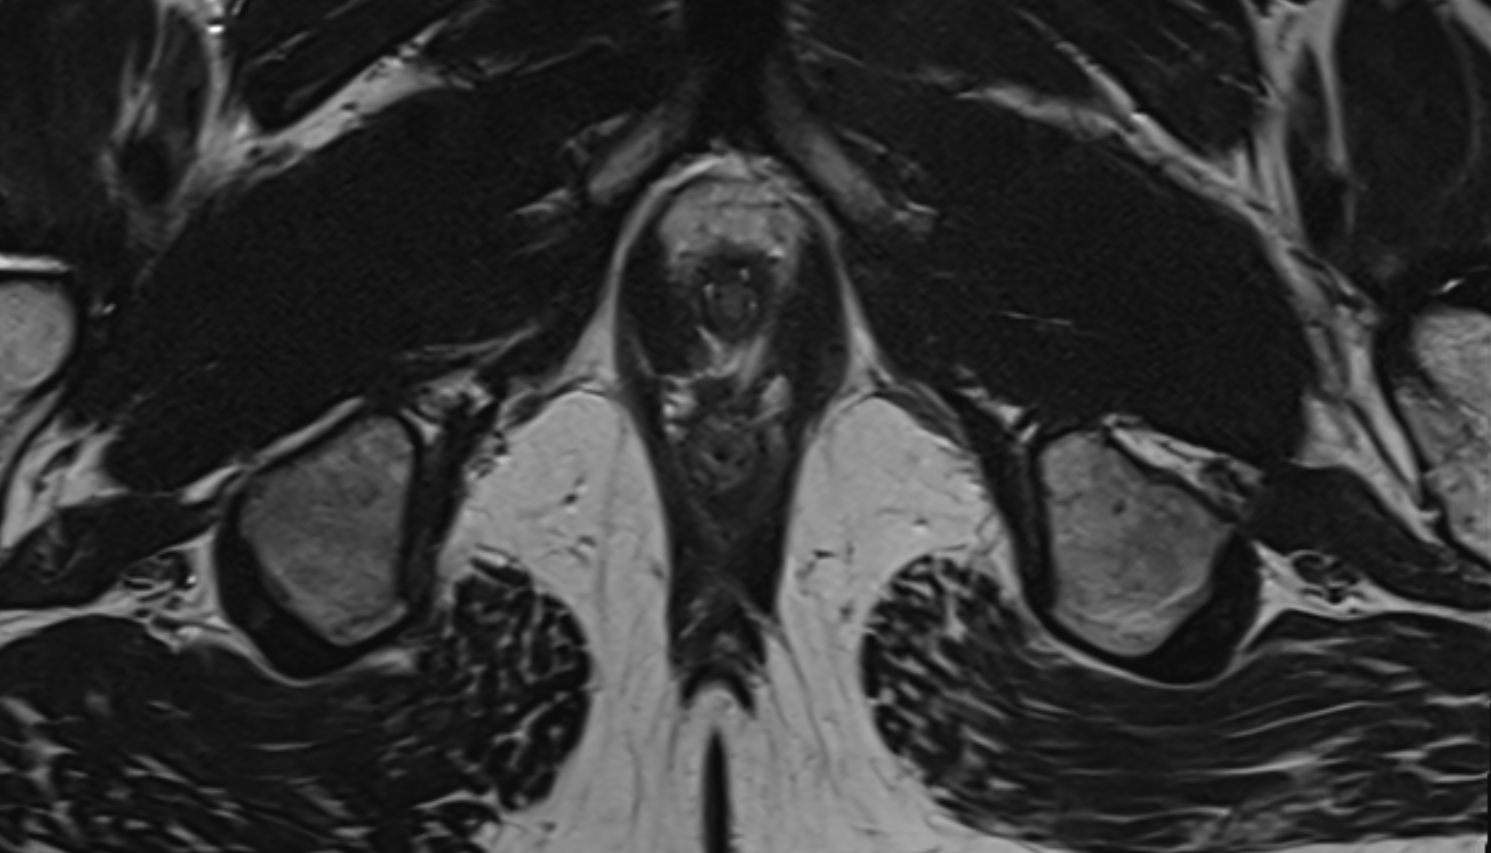

- Peripheral zone of prostate

- Anterior Fibromuscular Stroma of prostate

- Central zone of prostate

- Transitional zone of prostate